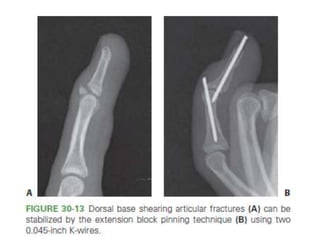

Middle Phalanx Fracture- Treatment Options

• Dynamic Extension Block Splinting.

– Volar base of P2 - less than 40% of the articular surface